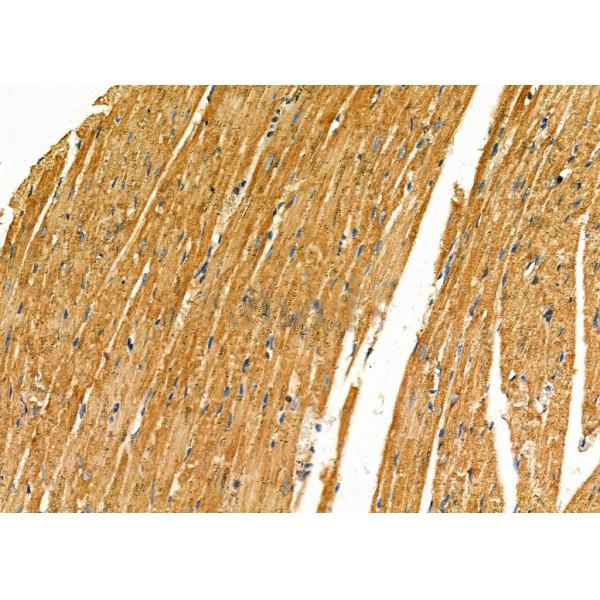

ab17073 at 1/100 staining Mouse heart tissue by IHC-P. The sample was formaldehyde fixed and a heat mediated antigen retrieval step in citrate buffer was performed. The sample was then blocked and incubated with the primary antibody at 4°C overnight. An HRP conjugated anti-Rabbit antibody was used as the secondary antibody....

ab17073 at 1/100 staining Rat heart tissue by IHC-P. The sample was formaldehyde fixed and a heat mediated antigen retrieval step in citrate buffer was performed. The sample was then blocked and incubated with the primary antibody at 4°C overnight. An HRP conjugated anti-Rabbit antibody was used as the secondary antibody....